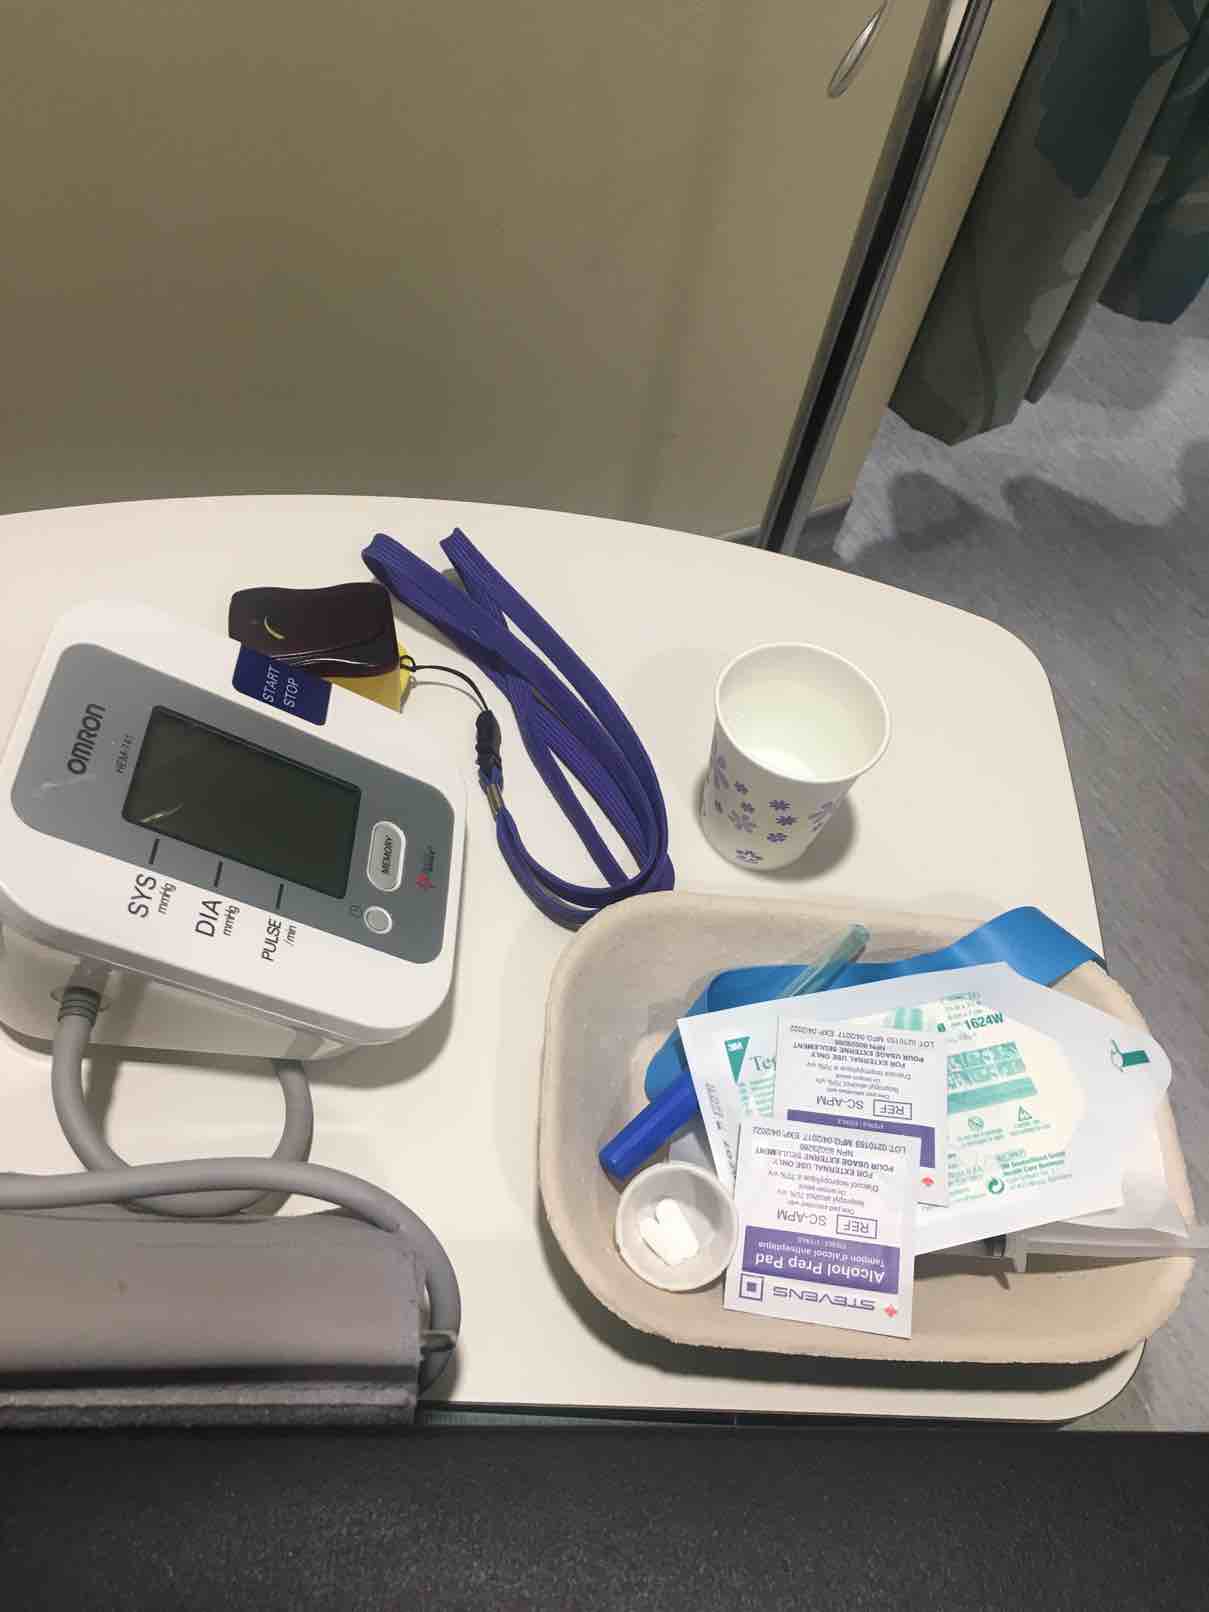

本人女29未婚未育手术前偶尔知道可以冷冻卵子 前提是要在化疗前做大家都知道化疗药物复合卵巢子宫都有一定副作用。一般医生都是建议内分泌药吃五年才可以考虑生孩子 生完继续内分泌五年我自己认为越年轻卵子质量也越好 数量可能也会相对高一点当我五年后34岁 我的卵子还是29岁的状态 而且是未受化疗药物污染的。我觉得为什么不尝试呢以下就来亲说我的取卵过程第一次去咨询的时候做了阴超显示可能有15颗左右卵子第二次是月经来的第二天 又检测了一下卵子 查了血接着自己回家打menopur 75IU ➕ purogan 225IU 每天还要吃一颗来曲挫到第五天的时候去诊所验血 下午通知加打一针orgalutran 接下来的10天左右都是每天定点自己在肚子上打三针 最后五天开始每天检测卵泡大小是否超过17mm到了周一终于不用再打针了 因为周二可以取卵了我没有做全麻 首先做椅子上吃了止痛药 放松的药 还有打了头孢。时间差不多就走去手术室 准备手术术前医生先帮忙清洗下体感觉跟生孩子差不多的姿势 也不知道他弄了些什么 不痛 就是这时候开始打麻药了 有点晕接着正式开始手术 就看到屏幕里一根针插入卵泡把它慢慢吸走 接着换另一个卵泡接着吸一共吸了十分钟 就被告知手术结束了腿上轮椅回到休息室休息了一个小时 并且打了点滴 才让我不那么晕也不想吐了 回家接到电话 取出22枚卵子。成熟的可以冷冻的有9颗好吧虽然一残都没到。但我多了一条后路哪天想生孩子 至少我还有年轻且健康的卵子存在想想心里也舒服点不是么附上我这两周自己给自己打的针 还有最后那些黑黑的球球就是卵泡😁